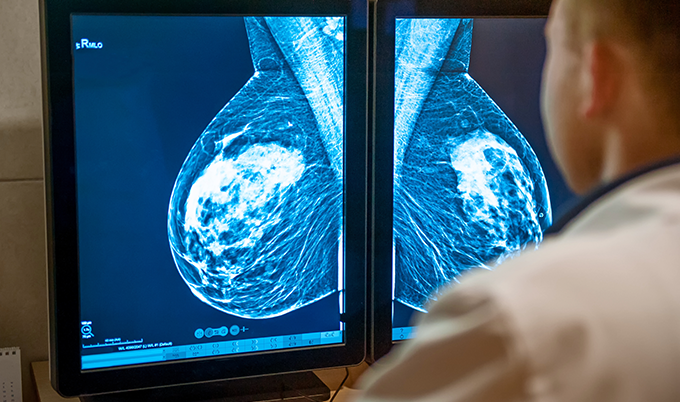

Diagnostic Mammogram

This is a more detailed version of what you just had, focusing specifically on the area of concern with additional angles and views. Diagnostic mammograms use targeted compression and magnification views to get a closer look at suspicious areas. The entire process typically takes 30-45 minutes.